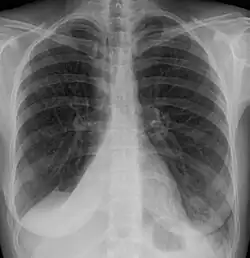

Atelectasis is the partial collapse or closure of a lung resulting in reduced or absence in gas exchange. It is usually unilateral, affecting part or all of one lung.[2] It is a condition where the alveoli are deflated down to little or no volume, as distinct from pulmonary consolidation, in which they are filled with liquid. It is often referred to informally as a collapsed lung, although more accurately it usually involves only a partial collapse, and that ambiguous term is also informally used for a fully collapsed lung caused by a pneumothorax.[1]

It is a very common finding in chest X-rays and other radiological studies, and may be caused by normal exhalation or by various medical conditions. Although frequently described as a collapse of lung tissue, atelectasis is not synonymous with a pneumothorax, which is a more specific condition that can cause atelectasis. Acute atelectasis may occur as a post-operative complication or as a result of surfactant deficiency. In premature babies, this leads to infant respiratory distress syndrome.

Clinically significant atelectasis is generally visible on chest X-ray; findings can include lung opacification and/or loss of lung volume. Post-surgical atelectasis will be bibasal in pattern. Chest CT or bronchoscopy may be necessary if the cause of atelectasis is not clinically apparent. Direct signs of atelectasis include displacement of interlobar fissures and mobile structures within the thorax, overinflation of the unaffected ipsilateral lobe or contralateral lung, and opacification of the collapsed lobe. In addition to clinically significant findings on chest X-rays, patients may present with indirect signs and symptoms such as elevation of the diaphragm, shifting of the trachea, heart and mediastinum; displacement of the hilus and shifting granulomas.[13]